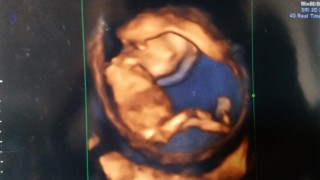

写真:14w0d:まうすさん

体外受精33回目にしての今のところ順調な妊娠生活。今日は、背骨の一本一本、肋骨も見えました!人間の生命力はすごいです!BPD24ミリです。

悪阻も治まりつつある中での検診。この日は寝てたのかあまり動いてはいませんでした。しかも背中を向けて、左手を耳の辺りに当てていて顔が見えませんでした(;_;)一緒に見ていた娘も顔が見えなかったので微妙な反応(笑)赤ちゃんの大きさは8.4cmで、順調でした。

BPD2.73cm